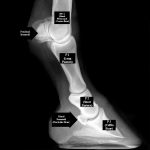

Cryptorchid - Types and Determination

Cryptorchidism in the colt

- This article describes the different forms, tests, resolutions and outcomes of cryptorchidism seen in the male horse (colt or stallion)....